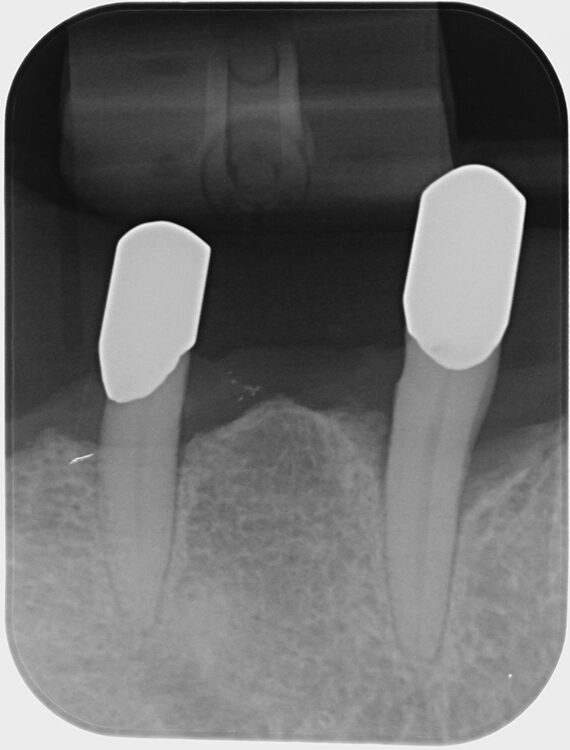

Abb. 3 a–e: Klinische Dokumentation eines 63-jahrigen männlichen Patienten (geb. 05.09.1961). Die Fotodokumentation erfolgte erst am Tag der AIT und nicht im Rahmen der klinischen und radiologischen und 47 wurden vor der AIT entfernt. An den Zahnen 13 und 23 war neben der peniblen subgingivalen Instrumentierung die Applikation von Straumann® Emdogain® (Straumann Group, Basel, Schweiz) vorgesehen.Walter

Abb. 3 a–e: Klinische Dokumentation eines 63-jahrigen männlichen Patienten (geb. 05.09.1961). Die Fotodokumentation erfolgte erst am Tag der AIT und nicht im Rahmen der klinischen und radiologischen und 47 wurden vor der AIT entfernt. An den Zahnen 13 und 23 war neben der peniblen subgingivalen Instrumentierung die Applikation von Straumann® Emdogain® (Straumann Group, Basel, Schweiz) vorgesehen.

Abb. 3f: Ausschnitt aus der Panoramaschichtaufnahme des in Abb. 3a-e dargestellten Patientenfalles. Deutlich wird der weit fortgeschrittene Attachmentverlust an nahezu allen Zähnen. Die ausgeprägte vertikale Komponente ist günstig für erfolgversprechende die Regeneration fördernde Maßnahmen.Walter

Abb. 3f: Ausschnitt aus der Panoramaschichtaufnahme des in Abb. 3a-e dargestellten Patientenfalles. Deutlich wird der weit fortgeschrittene Attachmentverlust an nahezu allen Zähnen. Die ausgeprägte vertikale Komponente ist günstig für erfolgversprechende die Regeneration fördernde Maßnahmen.

Es handelt sich hierbei um einen 63-jährigen männlichen Patienten (geb. 05.09.1961). Allgemeinmedizinisch war eine rheumatoide Erkrankung und die Einnahme von Methotrexat (Folsäureantagonist, Zytostatikum und Immunsuppressivum) dokumentiert. Etwaige orale Nebenwirkungen dieser Medikation lagen nicht vor. Herr B. war Nichtraucher. Der Patient wünschte maximalen Zahnerhalt und wurde daher zur parodontalen Therapie der bereits weit fortgeschrittenen Parodontitis an eine spezialisierte Praxis überwiesen. Zu diesem Zeitpunkt waren im Oberkiefer noch 2 und im Unterkiefer noch 5 Zähne vorhanden.

Der parodontale Screening-Index (PSI) an den verbliebenen Zähnen zeigte erhöhte Zahnlockerungen, stark entzündete und blutende Areale sowie Sondierungstiefen weit über 5 mm hinaus. Es lag dem zufolge ein Code 4* und damit die Notwendigkeit gründlicher Diagnostik vor. Die weiterführenden parodontalen Untersuchungen führten zur Diagnose einer generalisierten Parodontitis Stadium IV Grad C [46]. Die parodontal entzündete Wundfläche betrug 1088,69 mm2 [47]. Radiologisch konnten neben dem generalisierten horizontalen Knochenverlust auch ausgeprägte vertikale Defekte z.B. an den Zähnen 13 und 23 detektiert werden. Darüber hinaus wurde ein Chairside Vitamin-D-Test durchgeführt (Botiss, Straumann Group, Basel, Schweiz). Der Wert betrug 10 ng/ml und bedeutete, dass hier ein schwerer Vitamin-D-Mangel mit entsprechenden Implikationen für den Knochenstoffwechsel vorlag. Dem Patienten wurde eine Vitamin-D-Supplementierung mit zunächst 2000 IE und die Vorstellung bei seinem Hausarzt zu etwaiger weiterer Diagnostik und Festlegung einer optimierten Vitamin-D-Nahrungsergänzung empfohlen [48].